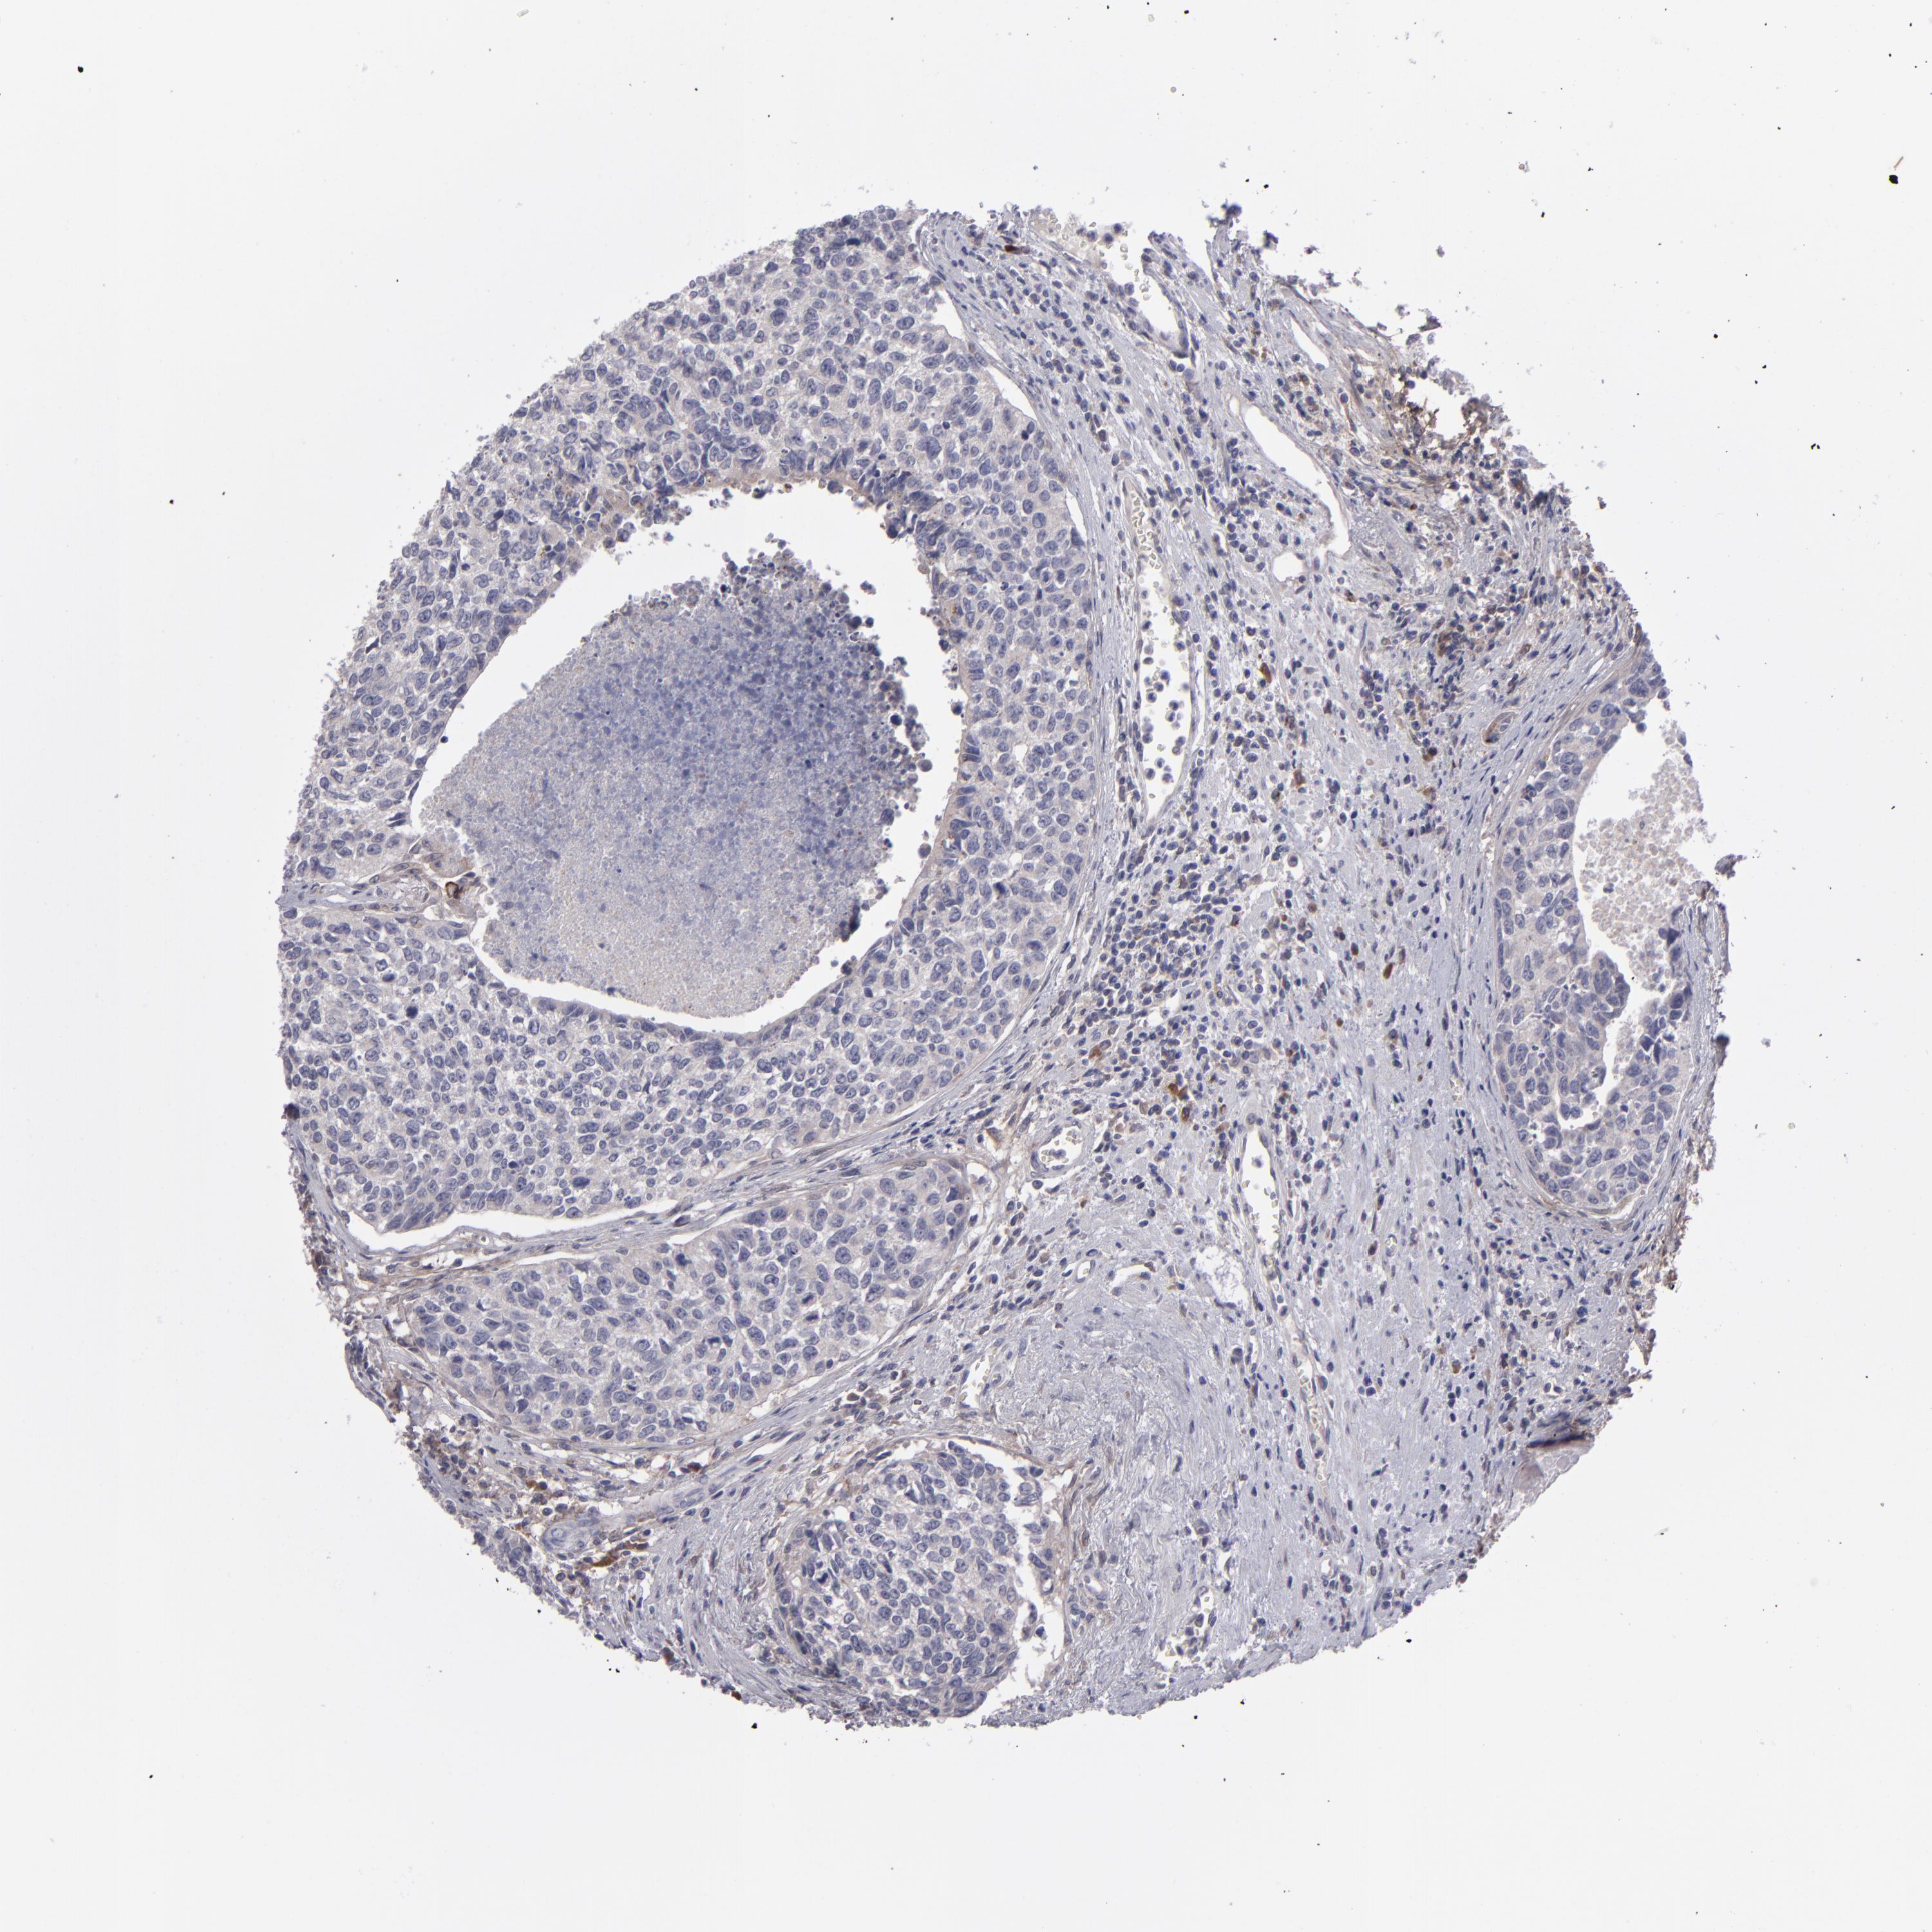

UROTHELIAL CANCER - Protein expressioni

A mouse-over function shows sample information and annotation data. Click on an image to view it in a full screen mode. Samples can be filtered based on level of antibody staining by selecting one or several of the following categories: high, medium, low and not detected. The assay and annotation is described here.

Note that samples used for immunohistochemistry by the Human Protein Atlas do not correspond to samples in the TCGA dataset.

Antibody stainingi

Antibody staining in the annotated cell types in the current human tissue is reported as not detected, low, medium, or high, based on conventional immunohistochemistry profiling in selected tissues. This score is based on the combination of the staining intensity and fraction of stained cells.

Each image is clickable and will lead to virtual microscopy that enables deeper exploration of all samples and also displays staining intensity scores, fraction scores and subcellular localization as well as patient and tissue information for each sample.

Antibody HPA001886

Staining

High

Medium

Low

Not detected

Intensity

Strong

Moderate

Weak

Negative

Quantity

>75%

75%-25%

<25%

None

Location

Nuclear

Cytoplasmic/membranous

Cytoplasmic/membranous,nuclear

Urothelial carcinoma, High grade

Urothelial carcinoma, Low grade

Adenocarcinoma, NOS